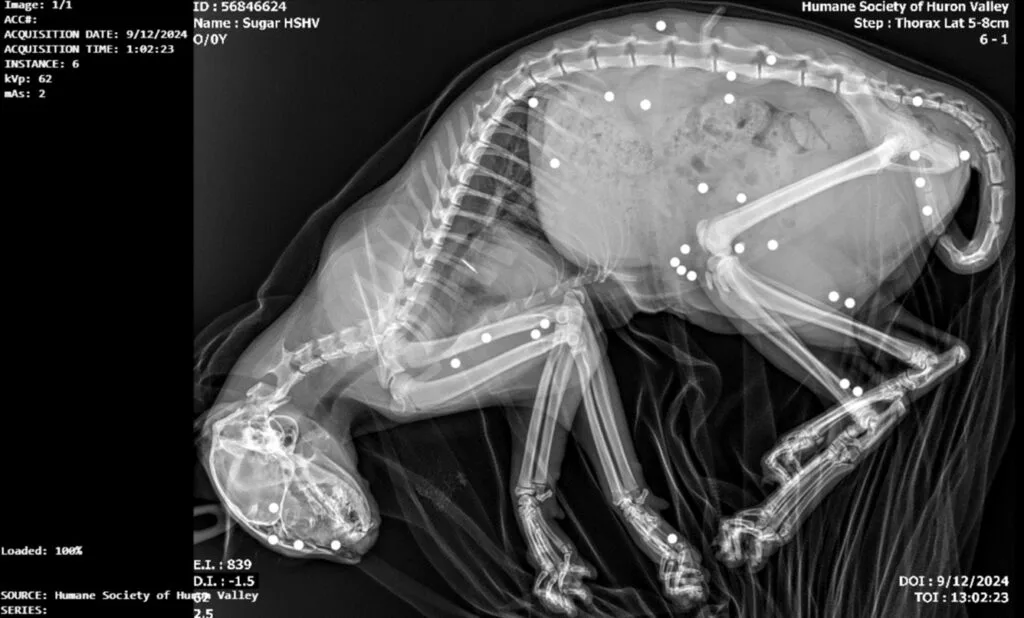

It wasn’t till the docs ran a sequence of X-rays that the total extent of the cruelty grew to become shockingly obvious.

The scans revealed that the little kitten, later named Sugar, had 35 BB gun pellets lodged all through her tiny physique—every one a brutal reminder of the violence she had endured.

The proof was irrefutable: Sugar had been used as goal follow by somebody who had as soon as cared for her. The thought was so horrifying that even the skilled vet was left speechless, unable to fathom how a defenseless creature could possibly be subjected to such cruelty.